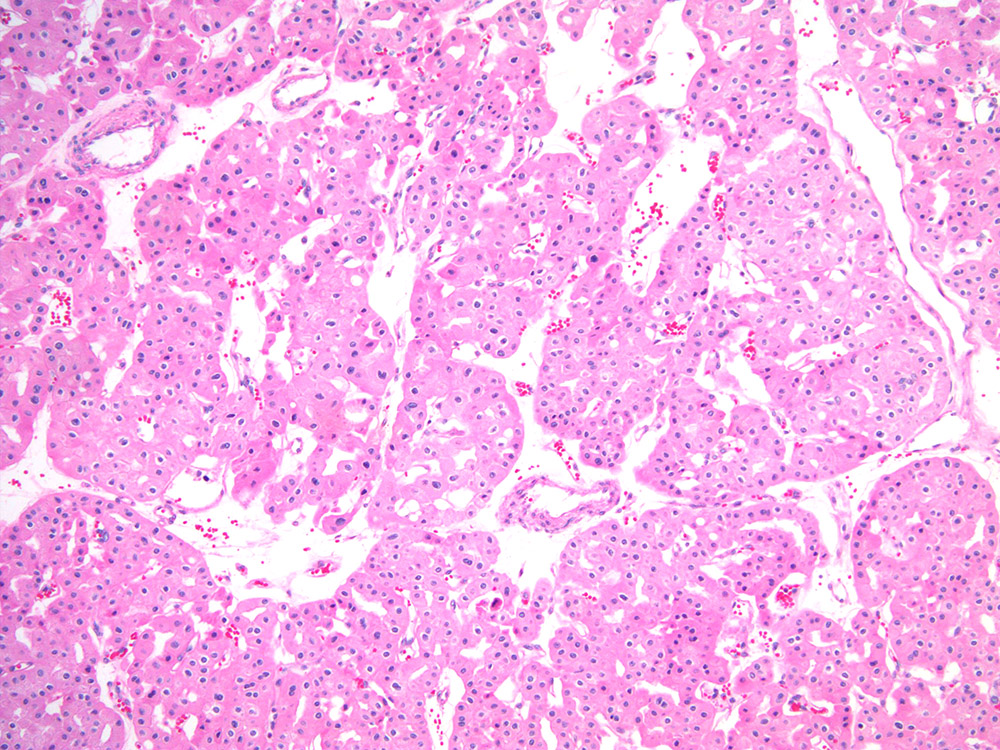

chromophobe RCC |

chromophobe |

Case description (by case creator):

Renal mass- 57 year old man